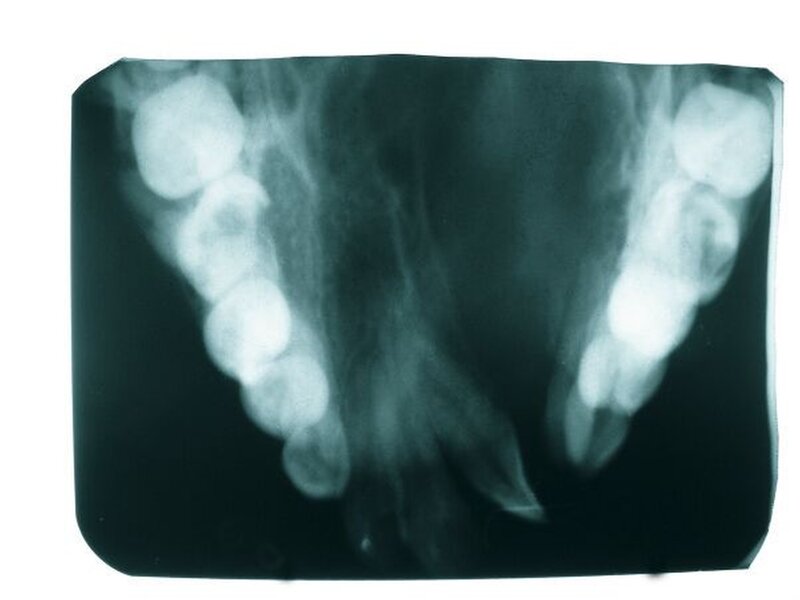

Die radiologische Untersuchung bestand aus einem Orthopantomogramm (OPTG), einer Aufbissaufnahme sowie einer Fernröntgenseitaufnahme (FRS). Neben der Übersicht der Gebissituation mit Nachweis des nicht durchgebrochenen Zahnes 22 im OPTG (Abbildung 3) war in der Aufbissaufnahme der Umfang der knöchernen Gaumenspalte klar zu erkennen (Abbildung 4). Das FRS ließ – bis auf die vertikal anterior verkürzte Maxilla und eine Protrusion der anterioren Prämaxilla – einen weitgehend normalen knöchernen Befund diagnostizieren (Abbildung 5).